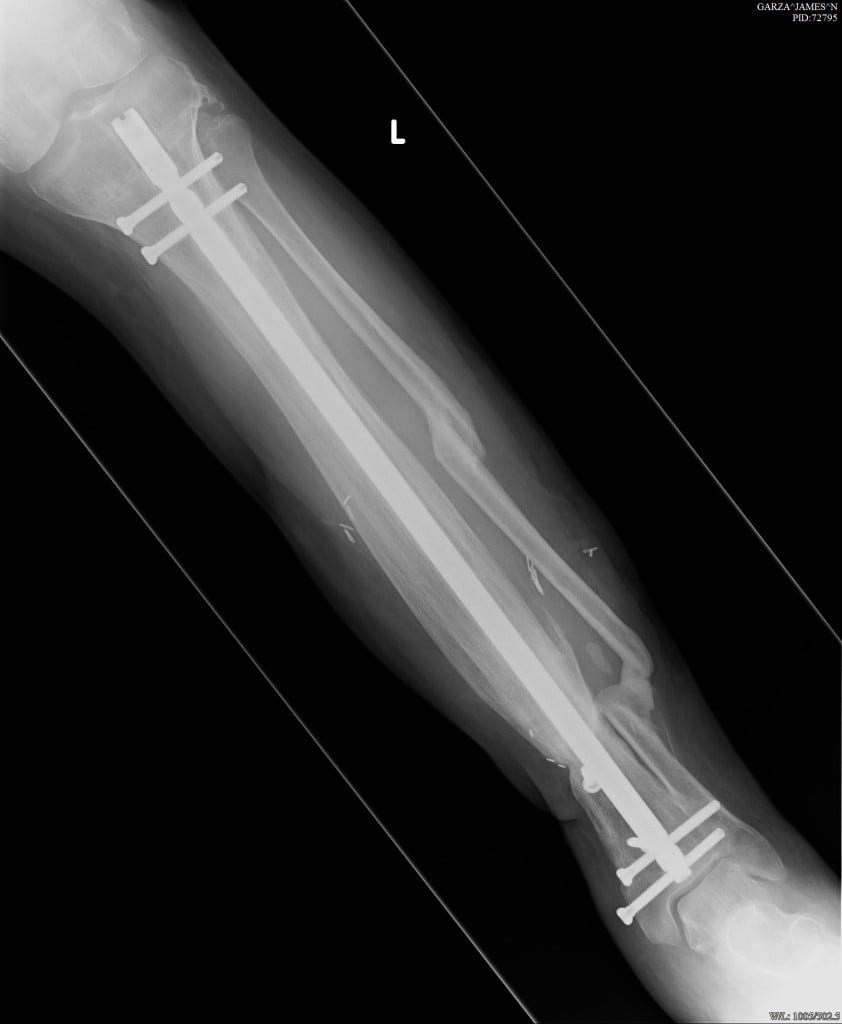

It was almost a year ago that we met in the middle of the night at NYP-ER. I have finally found the words to thank you. That night you saved my leg and now I walk without any visible sign of my accident and without any pain. I am still improving strength and balance with physical therapy. More important to me is that I believe you saved my life.